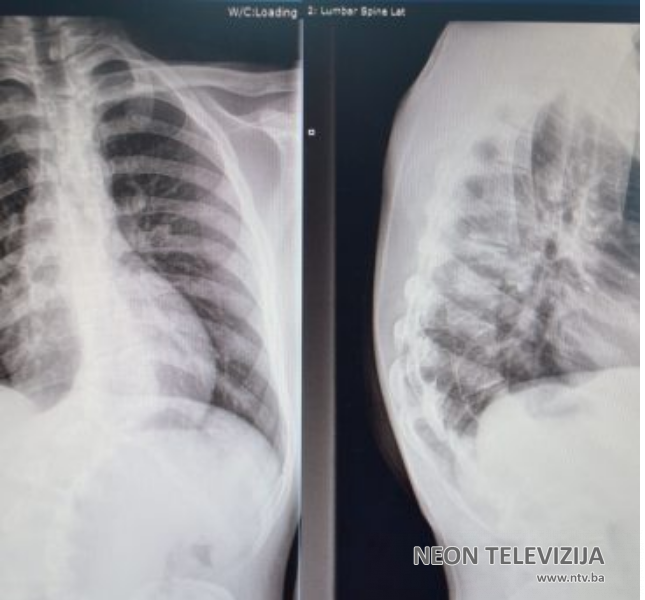

Prema riječima v. d. načelnika Klinike za ortopediju i traumatologiju UKC Tuzla, doc. dr. Aleksandra Vujadinovića, kod šesnaestogodišnjeg pacijenta iz Konjica urađena je ekscizija hemivertebrae prilikom koje je uklonjen abnormalano oblikovani pršljen kičmenog stuba. Kako je istakao doc. dr. Vujadinović radi se o operaciji kongenitalne skolioze, odnosno urođene skolioze koja nastaje zbog poremećaja u razvoju određenog dijela kičmenog stuba, konkretno pršljena. Poremećaj se javlja u periodu od 4. do 6. nedjelje intrauteriog razvoja, ne može se predvidjeti, niti spriječiti. Vremenom kako organizam raste i kako se kičmeni stub izdužuje tako se i deformitet povećava.

˝Mi smo po prvi put uradili operativni zahvat koji se sastoji od isjecanja i odstranjenja tog pršljena na način da usput izvršimo i korigovanje skolioze, koliko je to moguće u ovoj životnoj dobi, i tako spriječimo dalji nastanak deformiteta. Ova operacija je bila visokog rizika zbog mogućih neuroloških ispada, pa i oduzetosti donjih ekstremiteta, te smo prije operacije pacijenta i njegove roditelje upoznali sa mogućim rizicima. Operacija i postoperativni tok su protekli uredno i zadovoljni smo ishodom”, rekao je doc. dr. Vujadinović.